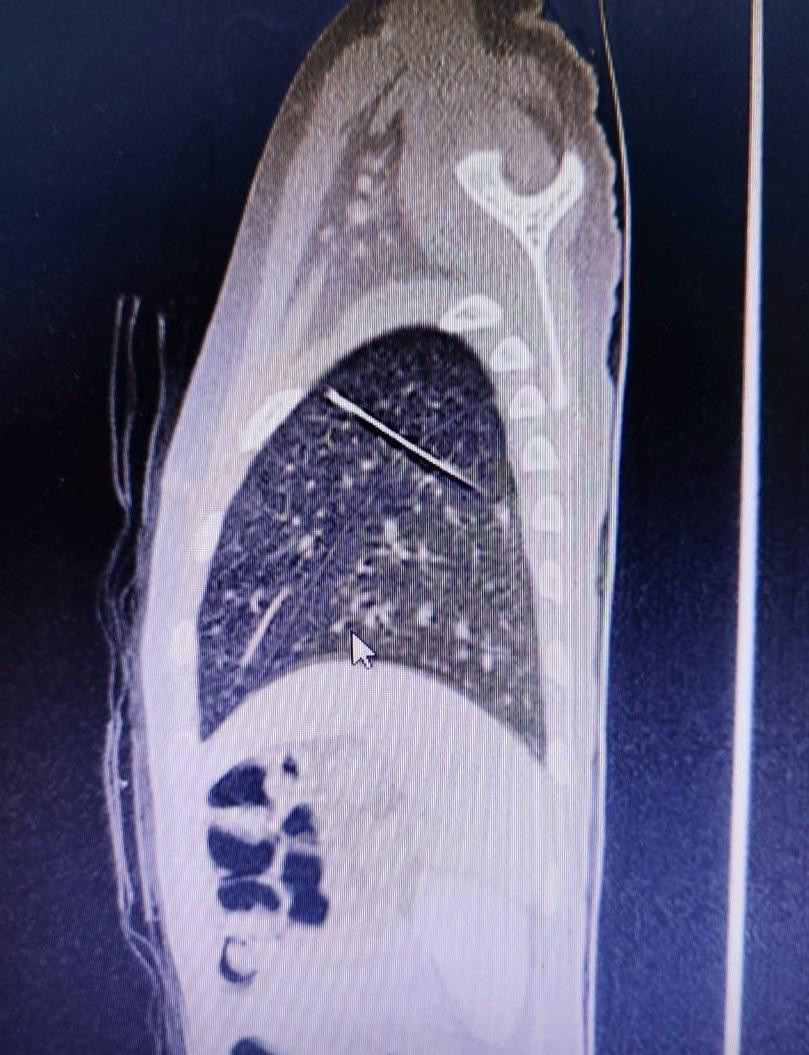

Tuy nhiên, trên phim X-quang, các bác sĩ tá hỏa phát hiện trong nhu mô phổi bên trái của bệnh nhi có dị vật cản quang dài và nhọn giống chiếc kim may vá đã xuyên từ thùy dưới lên thùy trên.

| Dị vật là chiếc kim (hình ảnh cản quang) nằm trong nhu mô phổi của bệnh nhi |